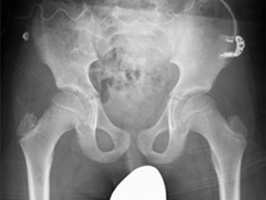

SkyFlow Plus

A grid-less workflow with SkyFlow Plus.

• Improves image contrast

• Saves an average of 34 seconds per chest exam vs. grid workflow***

• Allows for fewer retakes caused by grid misalignment

• Supports X-ray dose management

• Fully automatic, patient adaptive, works without special attention